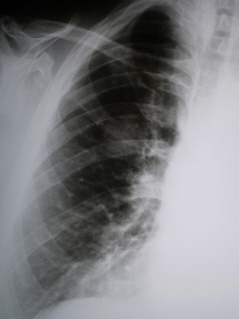

Цифровое стандартное флюорографическое профилактическое исследование (проведено на цифровом флюорографе «Ренекс – Флюоро»). На цифровой флюорограмме, произведенной в прямой стандартной проекции (илл. 1) справа на уровне 2 ребра определяется фокусная тень округлой формы размерами 3,5 х 3,7 см., средней интенсивности, довольно однородной структуры, с довольно ровными, но нечеткими контурами. На иллюстрации 2 – увеличенный фрагмент флюорограммы более четко определяется нечеткость контура фокусной тени.

Иллюстрация 3 и 4 – фрагменты рентгенограмм – правая половина грудной полости и фрагмент с увеличением – фокусная тень на уровне 2 ребра неоднородной структуры.

Иллюстрации 7 и 8 – томограмма в оптимальном срезе – 12 см. – фрагменты с увеличением. Фокусная тень округлой формы, размерами 3,2 х 3,5 см. средней интенсивности, неоднородной структуры – с мелкими просветлениями по медиальному и медиально-нижнему контурам. Местами на общем фоне фокусной тени намечаются не четко очерченные очаговые уплотнения. Контур по латеральному и нижнему краям неровный и не чёткий. Данная фокусная тень двумя «дорожками» соединена с корнем правого лёгкого. В корне мелкие обызвествления. От латерального контура объёмного образования «компоненты усиленного рисунка» - к костальной плевре.

Заключение: Периферический рак верхней доли правого лёгкого.